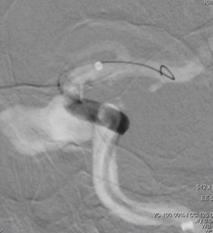

术前造影:

左侧颈内动脉C3段大动脉瘤,大小约23*11mm,瘤颈长度7.4mm,载瘤动脉远端直径约3.8mm,近端直径约4.2mm。

重新行3D造影,根据目标动脉瘤及载瘤动脉选择角度,路图下在0.014 Synchro2微导丝引导下将WILLIS®覆膜支架(4.5*16mm)准确定位至左侧颈内动脉C3动脉瘤位置。

6F Navien导管超选至动脉瘤远端,微导丝引导下WILLIS®支架到位。

球囊首次扩张,支架展开,首次造影图示动脉瘤近端贴壁不良,有造影剂渗漏至动脉瘤腔内,故再次充盈球囊扩张支架近端。